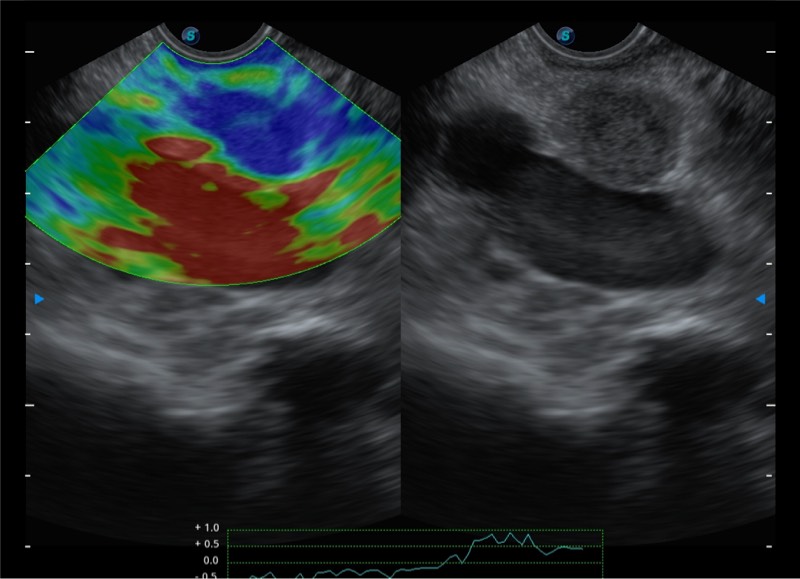

基于二十年的超声技术积累,银河优越会提供了最新一代的独立超声主机,在提供高质量图像的同时满足多学科使用。具备常见多普勒技术并提供弹性成像、声学造影等高端影像技术。新一代传感器具有更强的抗干扰能力并减少图像伪影。